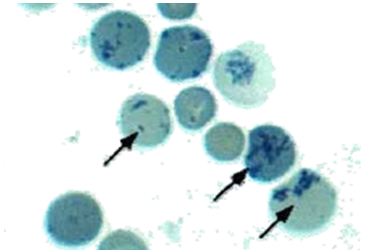

Otro de los genes estimulados por el HIF-1 es la eritropoyetina (EPO). Esta hormona glucoproteica renal estimula la síntesis en la médula ósea de nuevos reticulocitos, precusores de eritrocitos. En el último termino aumenta la aportación de oxigeno a nivel sistémico.

Figura 3. Reticulocitos nuevos (señalados con un cuadro), paso de eritroblasto a hematíe. El punteado se debe a que restos de ARN (del núcleo del eritroblasto)

precipitan con ciertos colorantes vitales como el azul de metileno o el azul brillante de cresil. La cantidad de precipitado va disminuyendo al ir madurando el reticulocito